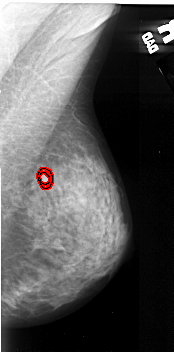

FILE: A_1057_1.RIGHT_MLO.OVERLAY

TOTAL_ABNORMALITIES 1

ABNORMALITY 1

LESION_TYPE MASS SHAPE OVAL MARGINS ILL_DEFINED

ASSESSMENT 4

SUBTLETY 4

PATHOLOGY MALIGNANT

TOTAL_OUTLINES 2

BOUNDARY

CORE